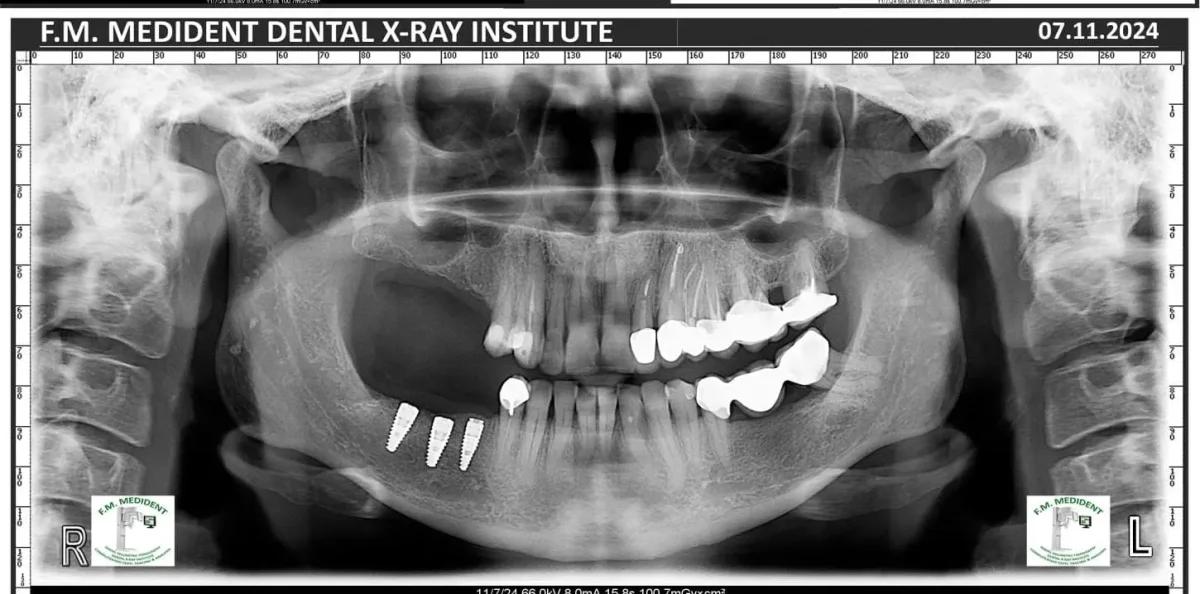

Cazuri reale înainte și după, din tratamente realizate în clinică.

Înainte

După